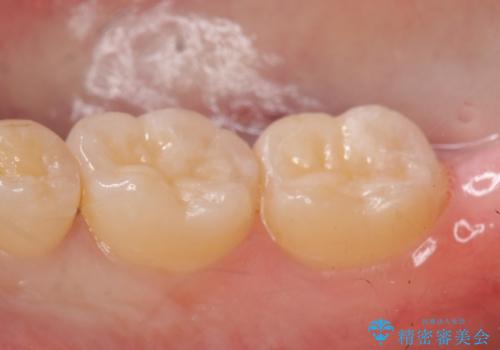

- 右下の一番奥の歯で冷たいものを飲むとしみるので診て欲しいといらっしゃった方の症例です。

ついでに銀歯もやり替えたいとのことだったので、右下6、7番目の歯に対してセラミックインレーによる修復を行いました。

当院のセラミックインレーはemaxという強度と審美性に優れた材料を使用しています。

またプレス方式でインレーを製作しているため、削り出しで製作するCADCAMより優れた適合性も持ち合わせており、虫歯が再発しにくい修復物です。